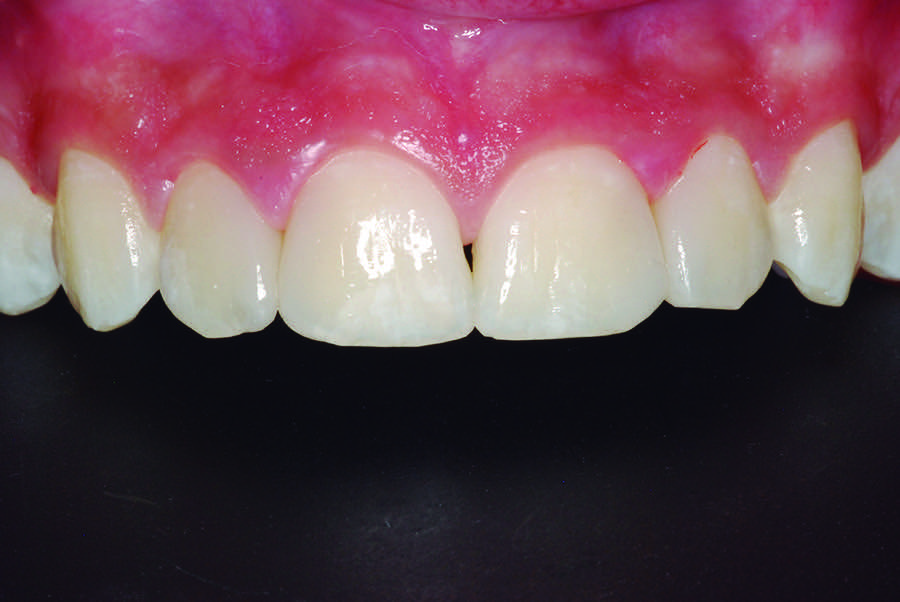

A 12-year-old male presented with extensive carious lesions observed on teeth Nos. 7 through 10, which were accompanied with gingivitis (Figure 1). The pulpal condition was verified through thermal sensitivity tests and vertical percussion, both being satisfactory (Figure 2). The proximity of the lesions with the pulp chamber and the absence of periapical lesions, especially in the right lateral incisor, were observed by the radiographic examination (Figure 3).

Fig 1. Initial aspect showing decayed teeth and gingivitis.

Figure 1